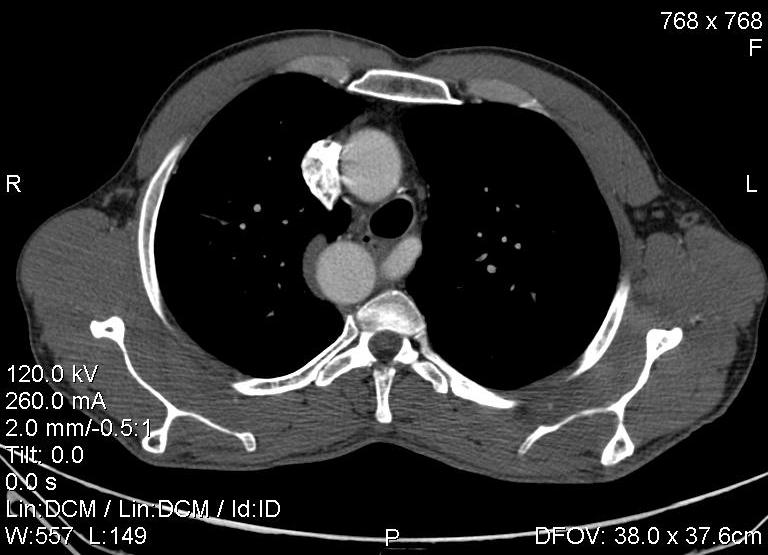

Пациент был направлен на КТ после рентгенографии ОГК, с направительным диагнозом: объёмное образование верхнего средостения.

это аномально расположенная грудная аорта

Конечно, дуга аорты идёт справа от позвоночника (декстра позиция); но есть и ещё одна аномалия той же группы: